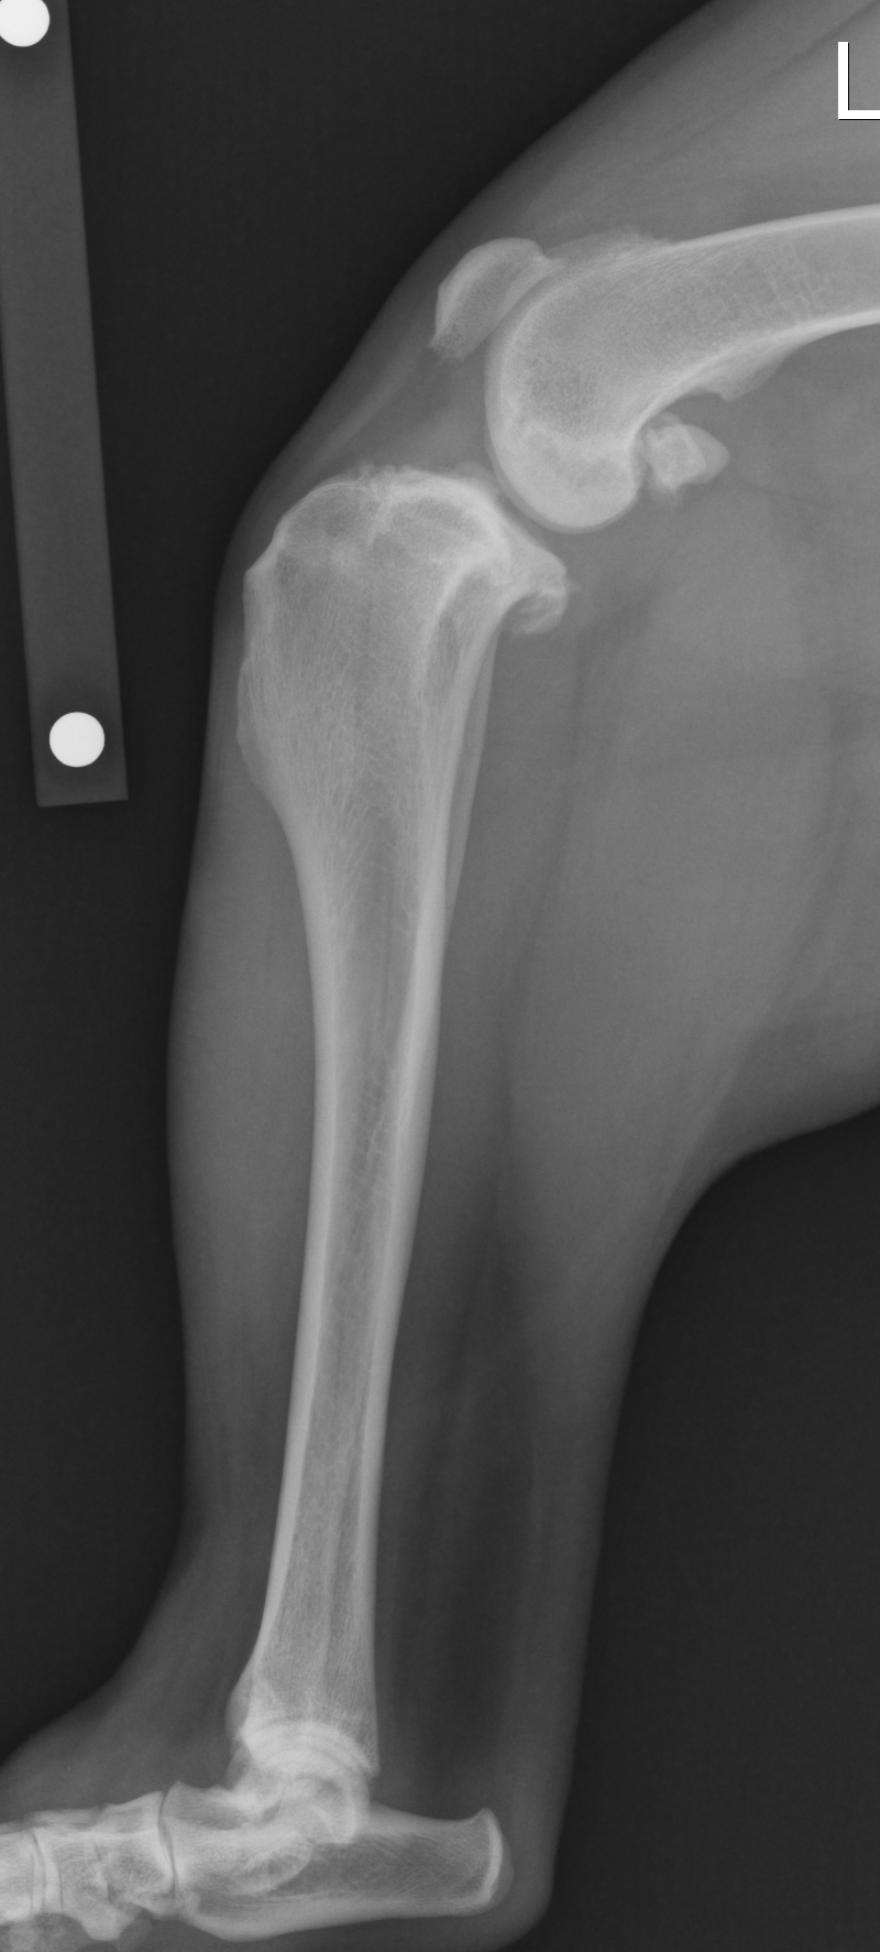

Radiographs: Classic radiographic findings are joint swelling, arthritic change and subluxation (forward movement) of the tibia in relation to the femoral. Classic areas of arthritic development are the patella, fabella, tibial plateau and femoral condylar ridges. I recommend the radiograph (x-ray) be taken with the knee and hock in 90 degree flexion. Please note the differences of the normal and affected knee in the radiographs attached. The benefit of radiographs for me is to see mild changes to confirm the diagnosis and to derive my measurements for either the tibial plateau leveling osteotomy (TPLO) or tibial tuberosity advancement (TTA) procedures.